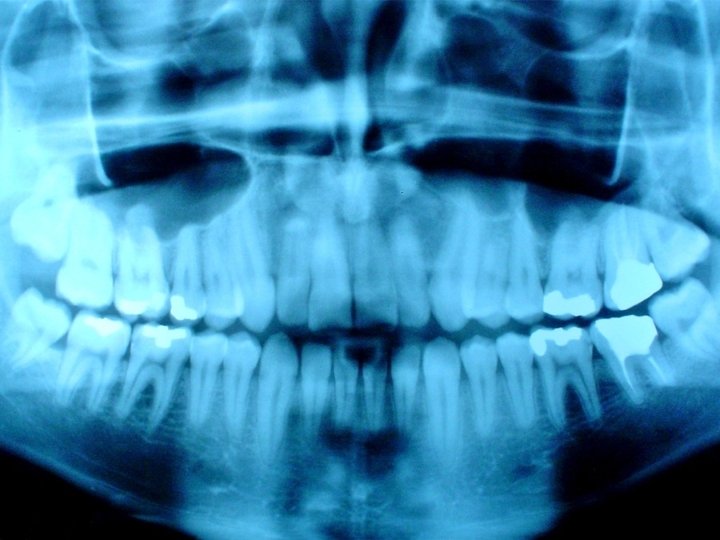

Dental X-rays

Forensic Odontology • • Peculiar shapes of teeth Root canal on x-ray Bone pattern on x-ray Bite patterns